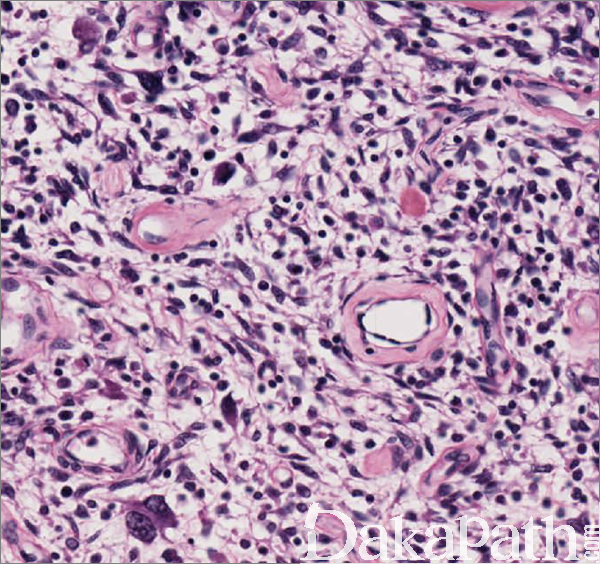

镜下肿瘤由密集排列、大小较为一致的短梭形瘤细胞和大量小到中等大的厚壁血管组成,分布于水肿或纤维性间质之中;

梭形细胞密度较高、呈短束状排列为主,偶见栅栏状排列;瘤细胞胞界不清,胞浆嗜酸性或浅染,核形态温和、卵圆形纺锤状,核仁不明显,核分裂象通常稀少,但偶尔可达 10 个/10HPF;

6,瘤细胞之间可见纤细的绳索样胶原以及数量众多的厚壁血管,血管腔隙开放呈圆形或卵圆形,偶见不规则分支,血管壁可见玻璃样变性;

瘤细胞间质可见水肿、透明变或黏液变性,在男性患者较为多见;间质常见肥大细胞浸润和血管周的淋巴细胞灶状聚集;